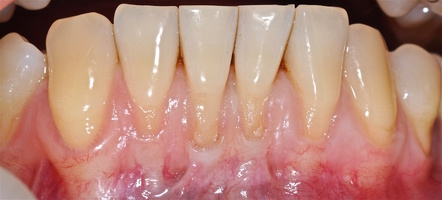

Был выбран и согласован следующий план лечения рецессий десны:

1. Генерализованные рецессии в области нижней челюсти оперировались в один этап все 12 зубов, фронтальный участок с аутотрансплантатом от 3.2 до 4.2 зубов. А дистальные участки от 3.6 до 3.3 и от 4.6 до 4.3 зубов с использованием пластического материала ТМО (dura mater) (рис. 4а-з).

4. Этапы хирургического лечения рецессий десны на нижней челюсти

3.2-4.2 зубы были прооперированы методом, сочетающим вестибулопластику с одновременным увеличением ширины и толщины прикрепленной десны при помощи свободного десневого аутотрансплантата (операция Bjorn, 1963 г.).